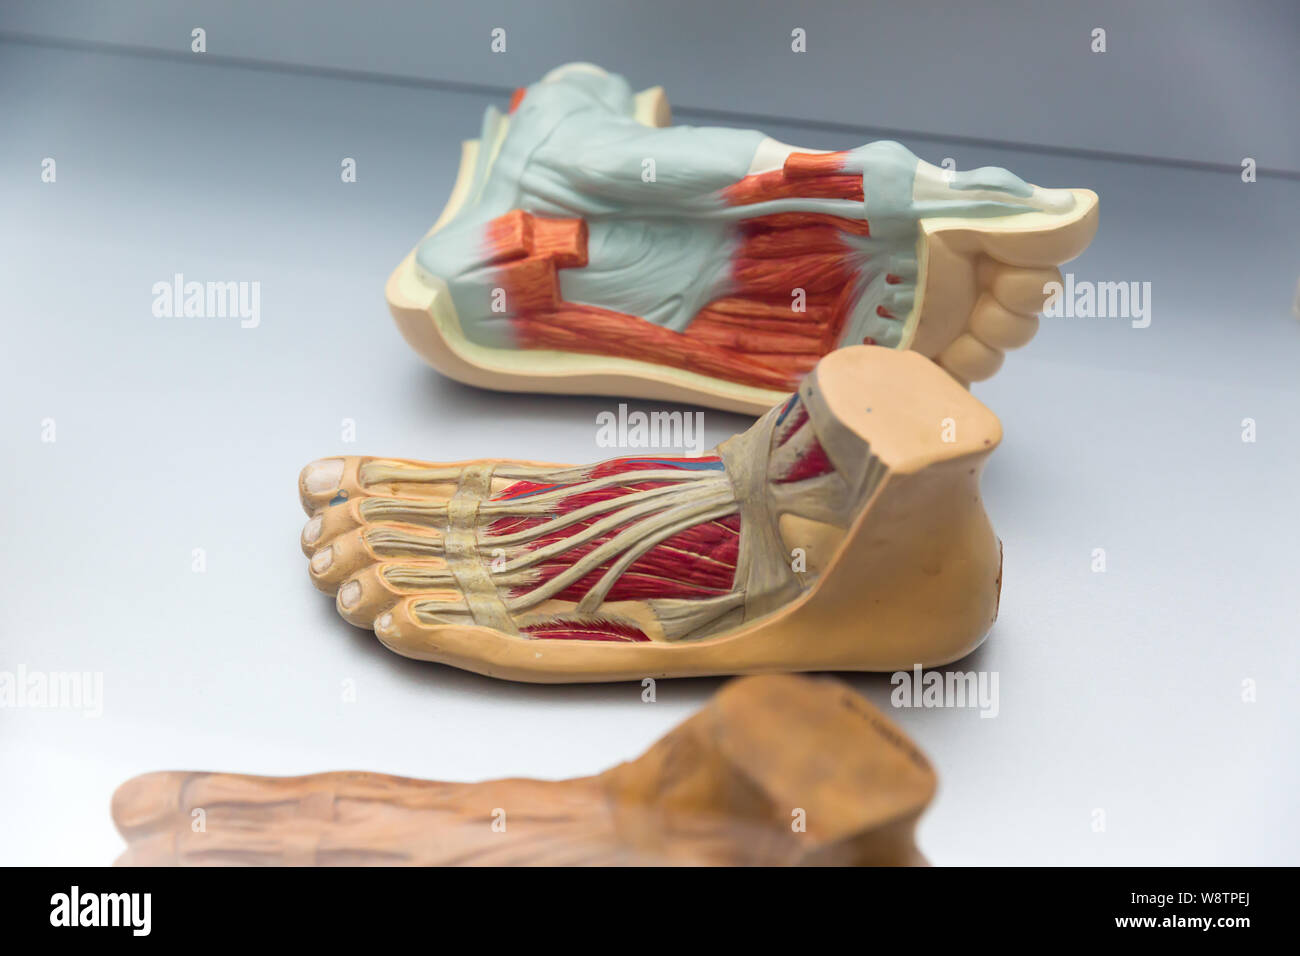

Anatomie du pied humain Photos Stock & Des Images

Anatomie du pied humain Photos Stock & Des Images